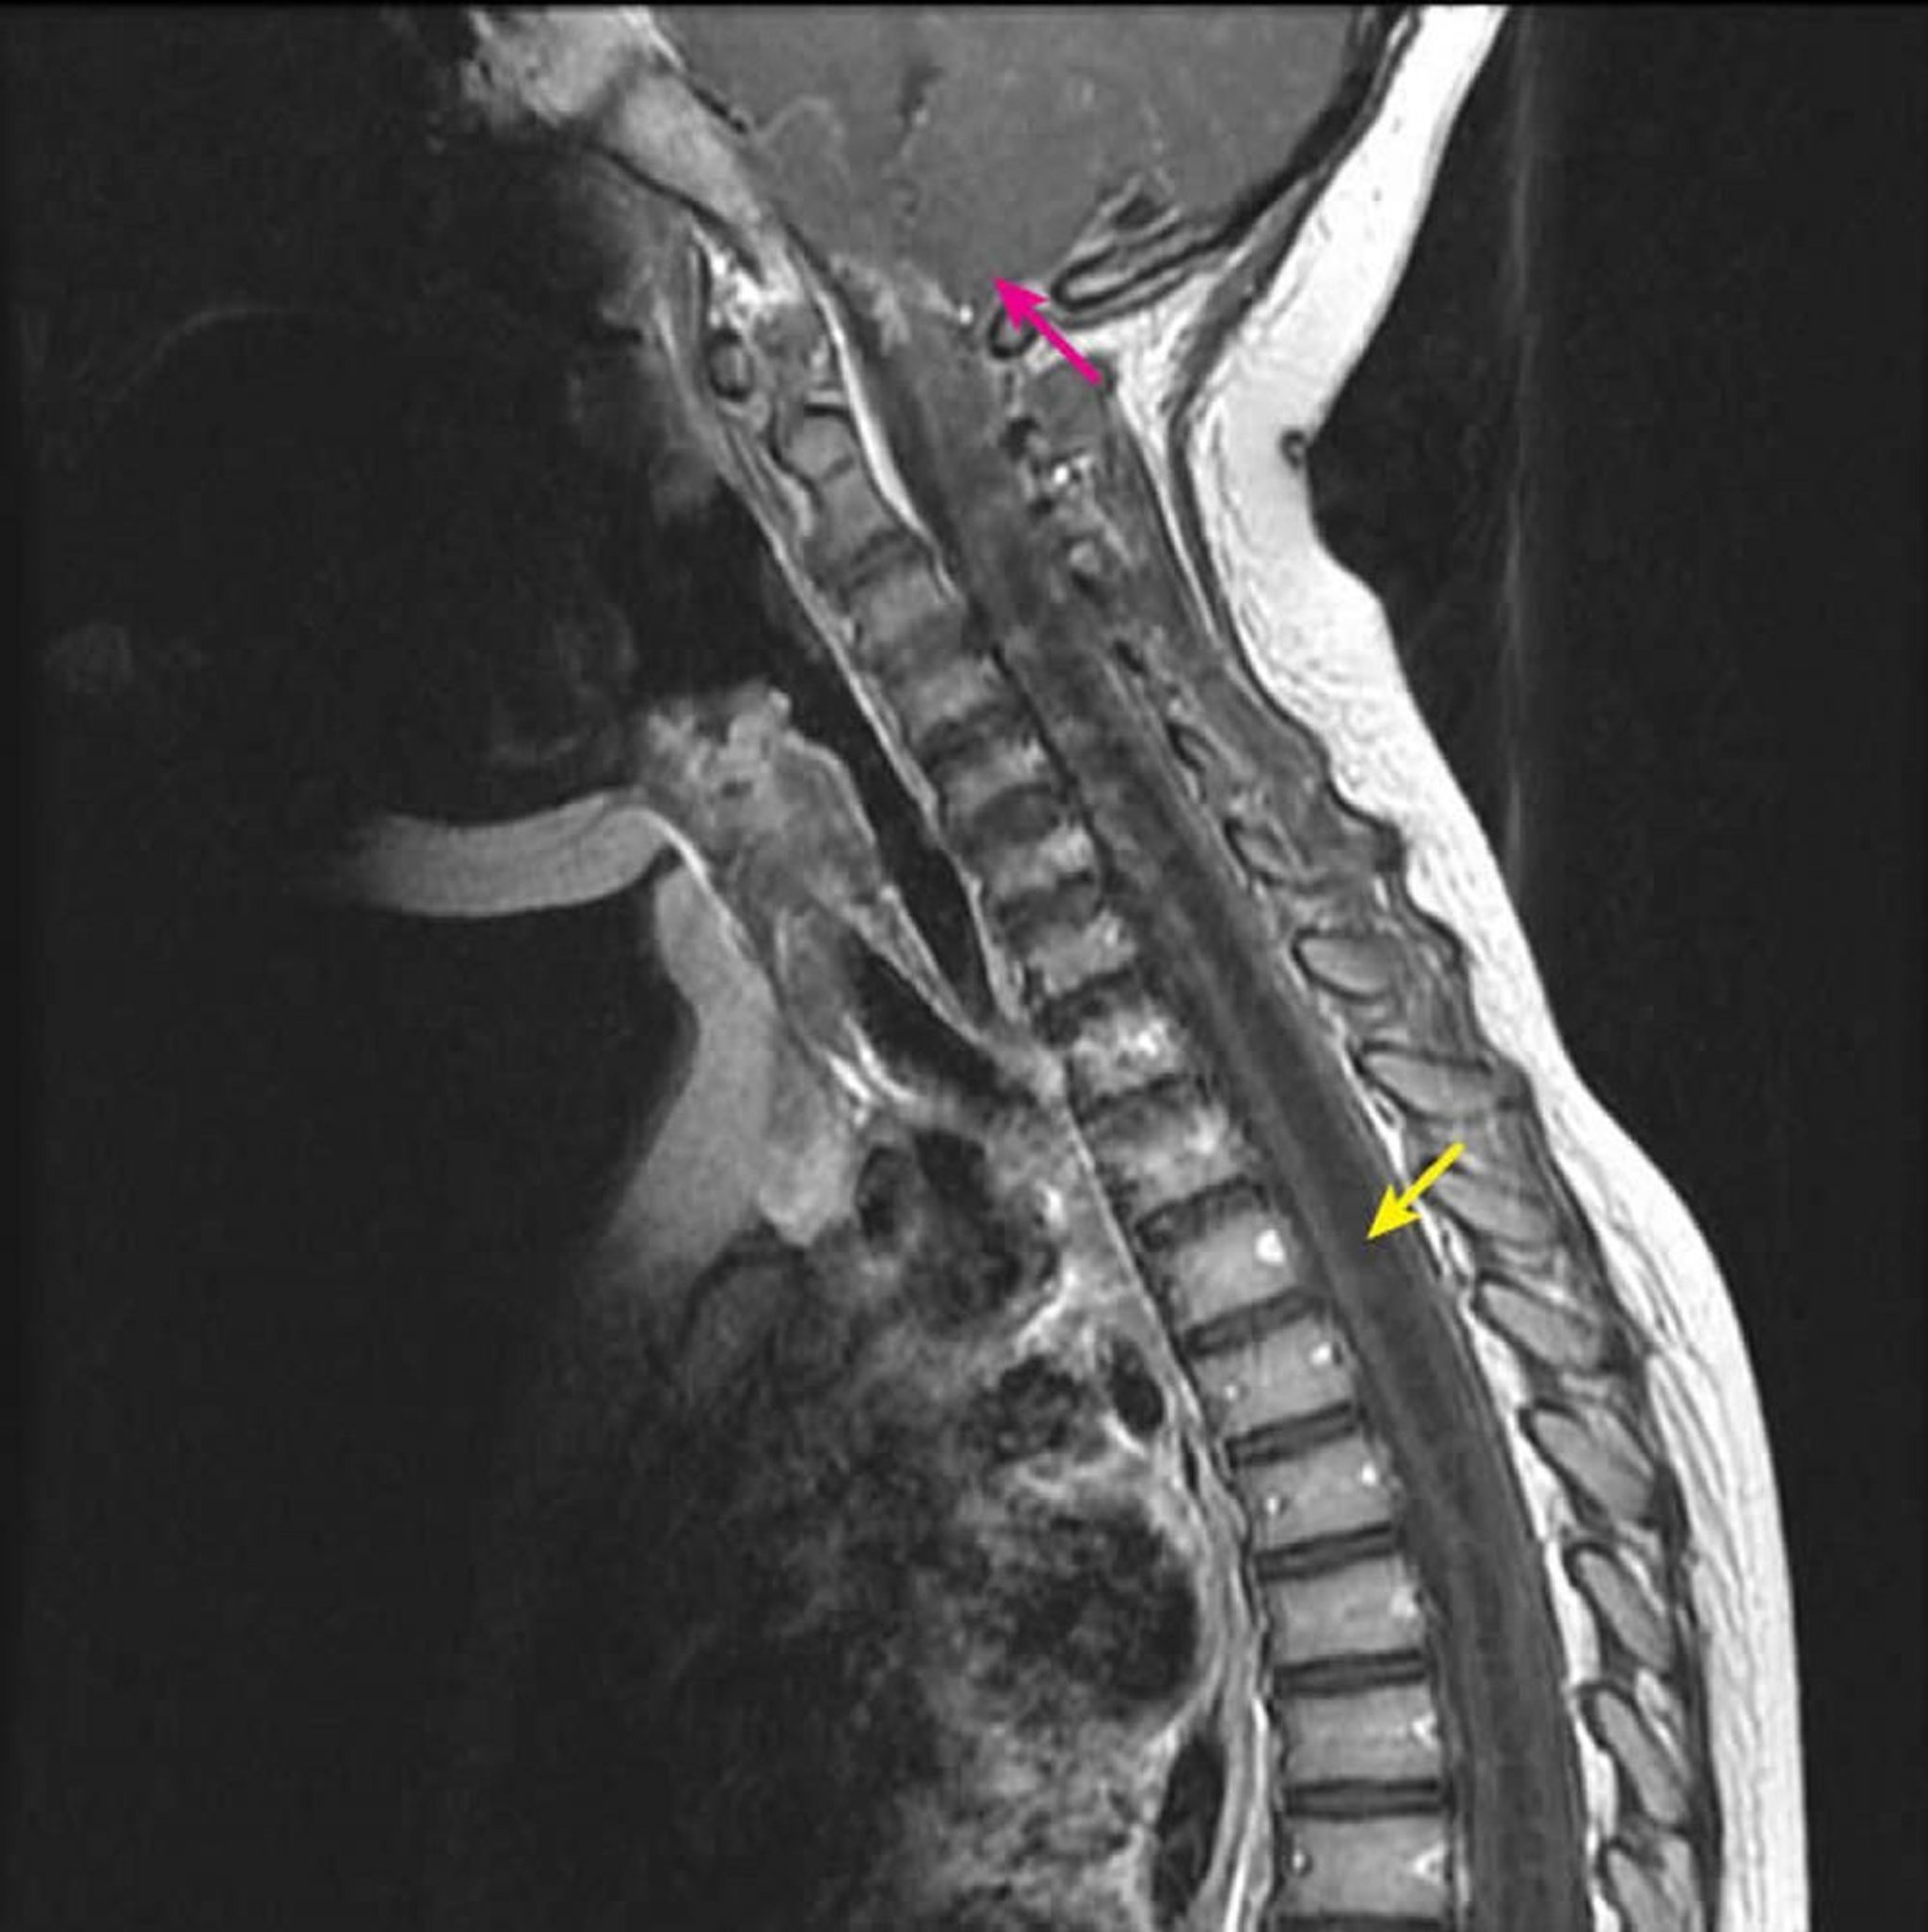

Zervikothorakale Syringohydromyelie

Die sagittale postkontrastive T1-gewichtete MRT zeigt eine große T1-hypointense intramedulläre Rückenmarkshöhle, die für eine Syrinx charakteristisch ist (gelber Pfeil). Bei einem Kind mit einer bekannten Chiari-I-Fehlbildung erstreckt sie sich von der C2-C3-Halswirbelsäule nach unten (rosa Pfeil). Dieser Befund wird als Syringohydromyelie bezeichnet, da die Syringomyelie (exzentrische Rückenmarkshöhle) durch die Bildgebung nicht von der Hydromyelie (zentrale Rückenmarkshöhle) unterschieden werden kann.